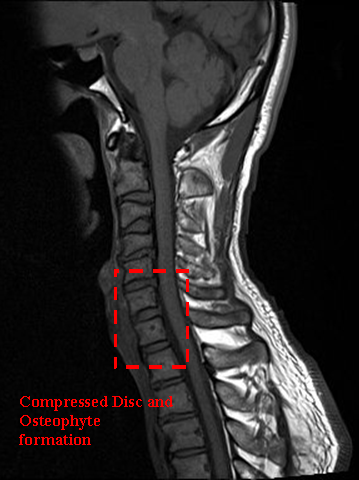

NECK INJURY, DEGENERATIVE DISC, & PINCHED NERVE

Mr. Sok Seila from Cambodia was involved in a terrible car accident. Since then, Mr. Seila often experienced severe pain at his neck region. Mr. Seila described the pain he felt as a stabbing pain in his neck, which caused him agonising pain and discomfort daily. Mr. Sok Seila undergone various medical and alternative therapies, however, none of them provided any relief.

MRI examination demonstrated degenerative discs at C4-C6, osteophyte formation and narrowing of Seila’s C4/C5 space. Mr. Seila started his stem cell treatment on March 2017. The decision was made to have Mr. Seila undergo cervical subcutaneous injection of 50 million stem cells and intravascular bolus injection (100 million stem cells).

4 weeks following the procedure, Mr. Seila reported an improvement in his condition, and he started to experience a significant decrease in his pain score several weeks later.